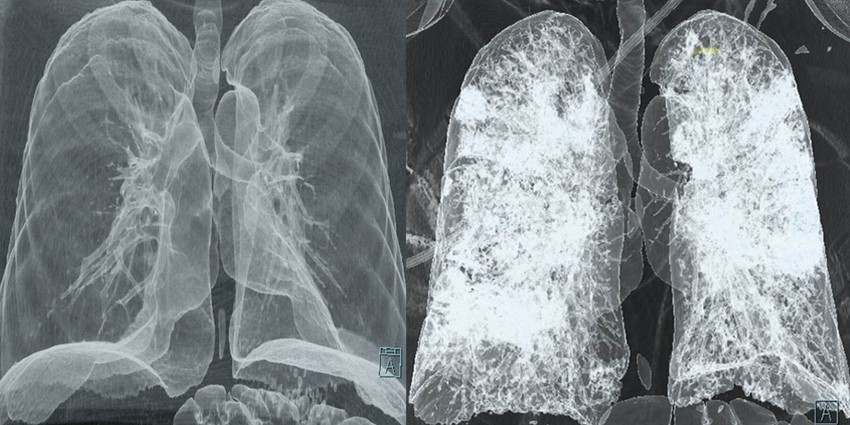

Balra: egészséges tüdő, CT-vizsgálattal rögzítve; helyesen: COVID-19-cel fertőzött személy tüdeje.

Forrás: https://aws.amazon.com/blogs/publicsector/helping-battle-covid-19-improve-cities-aws-cics-foster-innovation/